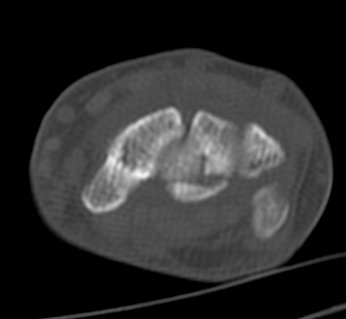

ÄÄÇ»ÅÍ ÃÔ¿µ :  ¿ù»ó°ñÀÇ ºÐ¼â°ñÀýÀÌ °üÂûµÊ(»çÁø 5, 6, 7, 8).